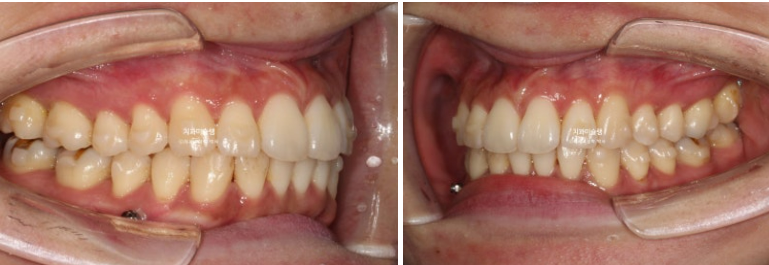

이제 전후 비교 보겠습니다.

23.08~25.11

총 치료기간은 2년 3개월이고 재제작 2회입니다.

현재는 비베라를 매일 잘 때만 끼면서 결과 유지중입니다.

교합의 균형이 맞아지면 비로소 좌우 50대 50으로 씹을 수 있게 됩니다.

교정치료가 심미치료라고 오해하는 분들 많으신대요 사실은 기능적으로 이득이 큰 치료입니다.